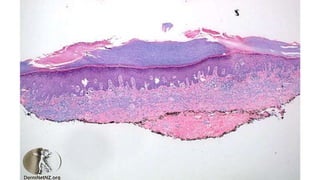

Histopathology of

Porokeratosis

Hereditary disorder of

keratinization characterized by

expanding atrophic anular patch(es)

surrounded by prominent keratotic

ridge called the cornoid lamella